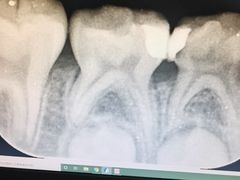

• 瑞尔齿科(颐堤港诊所)

• -瑞尔齿科(颐堤港诊所)

匿名用户 | 21-04-23